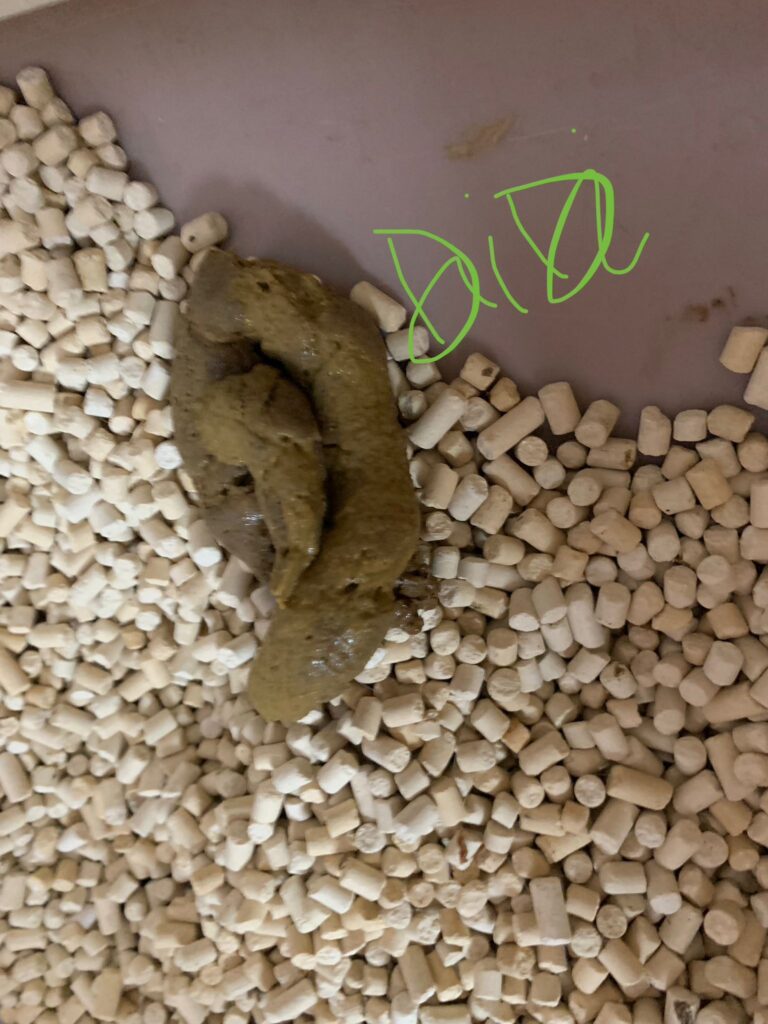

1pm: poo 4.5/10

Morning: didi constipated, saw him in 2 bins, trying to squeeze out something n can’t n he try to rub on floor – aren’t that pushing that piece in? I help him push out the 2cm piece 5/10, and he go to bin 03 and poo out another 12cm. So is that piece stuck n he is so uncomfortable. Subcut him w bupre also. His f patch still on. Can tear off soon. Need to buy more

Morning: sometime he will meow n meow at me. Want me sayang? In pain? Want some snacks? I sayang, f patch still on. I give him kelly n co fish don’t want, some Korean ciao like treat don’t want, given pidan prawn also don’t want. Have to think of what to bring over for him. Poo 4.5/10

Night: poo long n firm 5/10

7am+: he poo 1.5/10 w tinted blood. Reaction to niramine?

Morning: poo 3/10

Night: poo 1.5/10, w tinted blood

Night: poo 5/10, poo when i about to leave. Erm. Nice formed not much smell

Night: poo 3.5/10. Given him selar fish plate to munch after all the meds.

He poo 1.5/10, w blood (dr d says may be due to stress)

Poo 2/10 paste, given probiotics

1pm+: poo 2.5/10, give probiotics and nutriplus gel. Given Subcut w b12 bcom.

He poo again 2.25/10.

Morning: poo like ice cream cone texture, small smelly!!

7pm: poo 4.75/10. Happy to have some fish after pooing